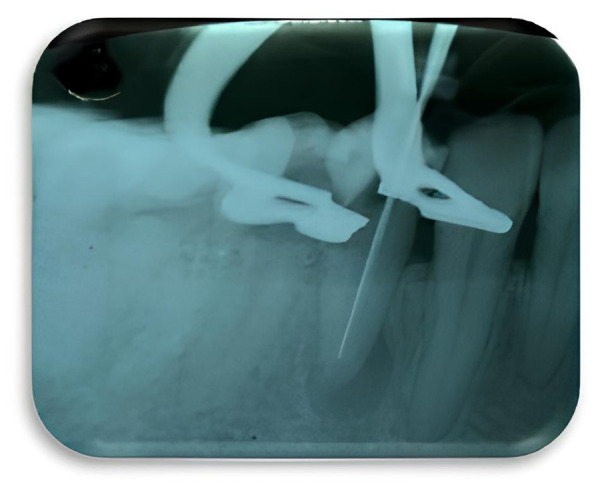

牙髓环境为微生物的生长提供了最佳条件,这些微生物会将副产品释放到牙齿根尖周围区域并引起炎性病变。使用刺激性溶液进行化学消毒在临床上发挥着重要作用,因为它们能够清除受污染的有机和无机组织中的废物,产生残留的抗菌效果。本研究的目的是显示 2.5% 和 5.25% 次氯酸钠作为冲洗剂在临床治疗一颗根尖吸收牙的慢性根尖周围脓肿中的有效性。最初使用的是 2.5% 的次氯酸钠,但由于 3 天后脓肿愈合反应并不理想,因此决定使用浓度为 5.25% 的次氯酸钠,以达到更好的杀菌效果。5 天后,瘘管愈合,牙髓治疗继续进行。本病例报告的视角之一是进一步研究抗生素治疗与良好冲洗方案的结合使用。

The endodontic environment has optimal conditions for the growth of microorganisms that can release by-products into the periapical region of the tooth and cause inflammatory lesions. Chemical disinfection using irritants solutions plays an clinical important role, as they are able to remove waste from contaminated organic and inorganic tissues, generating a residual antibacterial effect. The purpose of this study was to show the effectiveness of 2.5% and 5.25% sodium hypochlorite as an irrigating agent for the clinical management of a chronic periapical abscess in a tooth with apical resorption. Initially, 2.5% sodium hypochlorite was used, however, as it did not have an optimal abscess healing response after 3 days, it was decided to use a concentration of 5.25% to achieve a better bactericidal effect. After 5 days, the fistula healed, and endodontic treatment continued. One of the perspectives of this case report is to investigate more about the use of antibiotic therapy in conjunction with a good irrigation protocol.